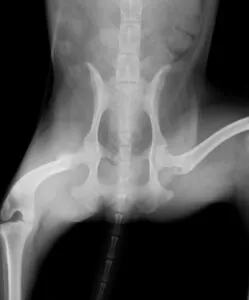

写真は両側の股関節脱臼をして整形外科の専門病院にて外科的整復を行った別症例。